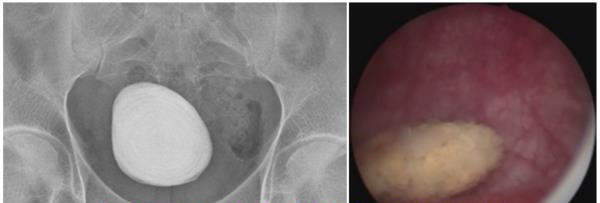

经尿道膀胱结石钬激光碎石术

该技术无需切口,通过尿道置入器械入膀胱,采用钬激光将结石粉碎后清除出体外。对肾输尿管结石排入膀胱而无法从尿道排出的情况,则需要行碎石术。对老年人膀胱结石,大多是继发于前列腺增生或者膀胱颈、尿道狭窄,则在术中清除结石后还需要同期处理这些原发致病因素,否则结石很容易再发。